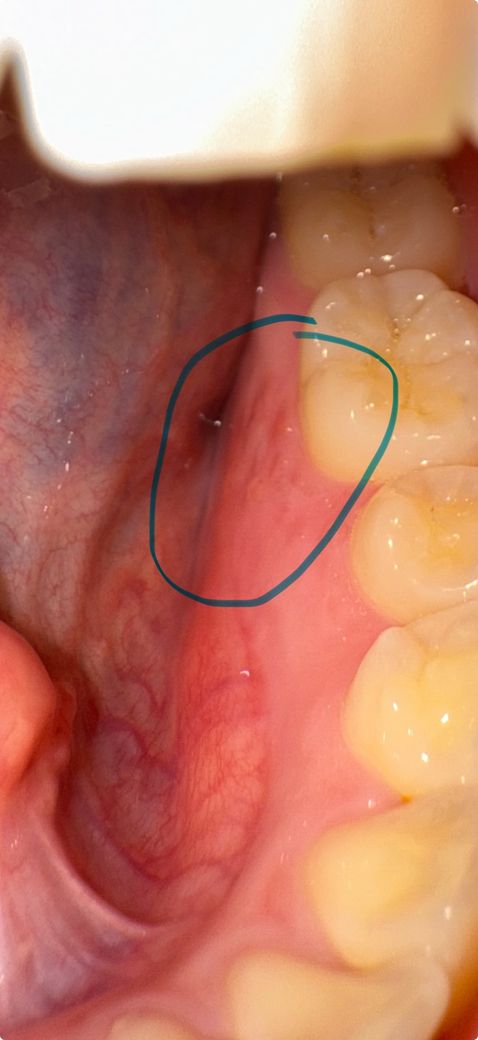

사진은 순서대로 목요일 - 금요일(어제) - 금일오전 - 금일 오후입니다. 처음엔 부어서 살이 울퉁불퉁 올라온 느낌(통증없음), 살짝 하얗게 수포처럼 올라옴 (통증 무), 염증 아문 듯한 빨간 흉터 (통증무), 오늘은 마치 긁힌? 패인? 듯한 염증자국 (혀로 건들면 정말 아주 조금 따끔)

혀로 만져보면 오늘은 실제로도 패인듯한 촉감입니다 ㅜ 네번째 사진에 허옇게 보이는 건 팝콘찌꺼기 일수도 있어요 (방금 먹고 찍었는데 억지로 빼긴 아파서 그대로 찍었어요ㅠ)

• 3번 째 사진